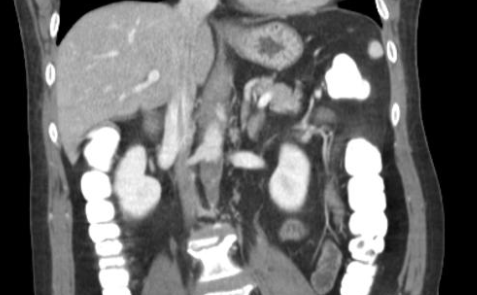

Cas

lereiche lerieche fontaine aorte aortique thrombus embol embolie occlusion iam syndrome lereiche